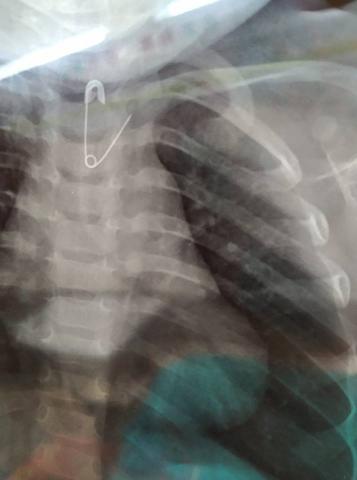

Σε πιο σοβαρές περιπτώσεις μπορεί να εμφανιστούν συμπτώματα όπως αίσθημα πνιγμονής, σιελόρροια, έμετος, δυσφαγία / άρνηση λήψης τροφής, συριγμός ή αναπνευστική δυσχέρεια. Για την εκτίμηση αυτών των περιστατικών, λαμβάνεται το κλινικό ιστορικό, καταγράφεται η ώρα κατάποσης, το είδος και μέγεθος του αντικειμένου ενώ ακολουθεί κλινική εξέταση και ανάλογα με το περιστατικό, ακτινολογικός έλεγχος (α/α θώρακος – κοιλιάς) για την εντόπισή του (αεροφόροι οδοί – οισοφάγος - στόμαχος)

Αν και ~65% των υλικών είναι ακτινοσκιερά, υπάρχουν αρκετά (π.χ. γυαλί – πλαστικό – ξύλο) τα οποία δεν “φαίνονται” στην ακτινογραφία , οπότε σε ισχυρή υποψία ή επί κλινικών συμπτωμάτων, είναι αναγκαία η περεταίρω εξέταση από ΩΡΛ ή η διενέργεια ενδοσκόπησης, και σπανιότερα άλλης απεικονιστικής εξέτασης

-Μεγάλα αιχμηρά αντικείμενα (καρφίτσες – παραμάνες – οδοντογλυφίδες) ελλοχεύουν κίνδυνο διάτρησης και συστήνεται να αφαιρούνται. Μικρότερα αιχμηρά αντικείμενα (πχ πινέζες) μπορεί προωθούνται στο πεπτικό αλλά χρήζουν παρακολούθησης (έως και 15 ημέρες) ώστε εάν ενσφηνωθούν για >72 ώρες ή επί ανάπτυξης κλινικών συμπτωμάτων επιπλοκών, να ακολουθηθεί ενδοσκοπική ή χειρουργική αφαίρεση (ανάλογα με την θέση τους).